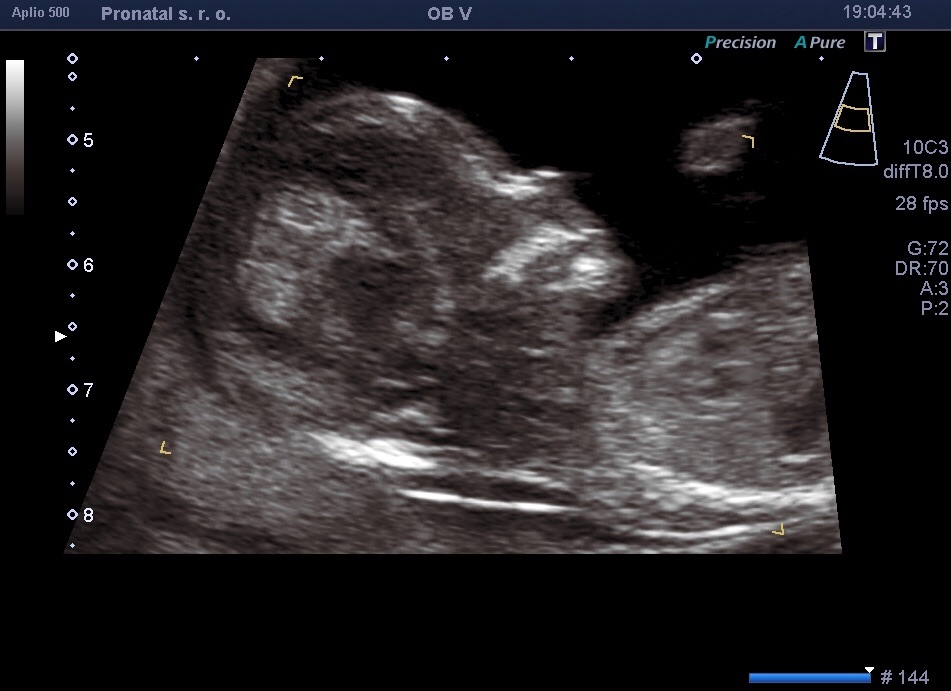

Ahoj holky, já měla první těhotenství molární (2012), rok jsem nesměla otěhotnět. Pak rok snažení a nic. Šli jsme tedy do CAR (Pronatal Praha) krevní testy hormony ok, dostala jsem Clostík 3.-7.den cyklu. 12.den UTZ foliků. Dva velké. Večer jsem si píchla injekci a za dva dny šla na první IUI. Přitom zrovna udělali spermiogram, který dopadl moc dobře. No a dole vidíte výsledek. Teď jsem 15+6tt. Držím všem palce!